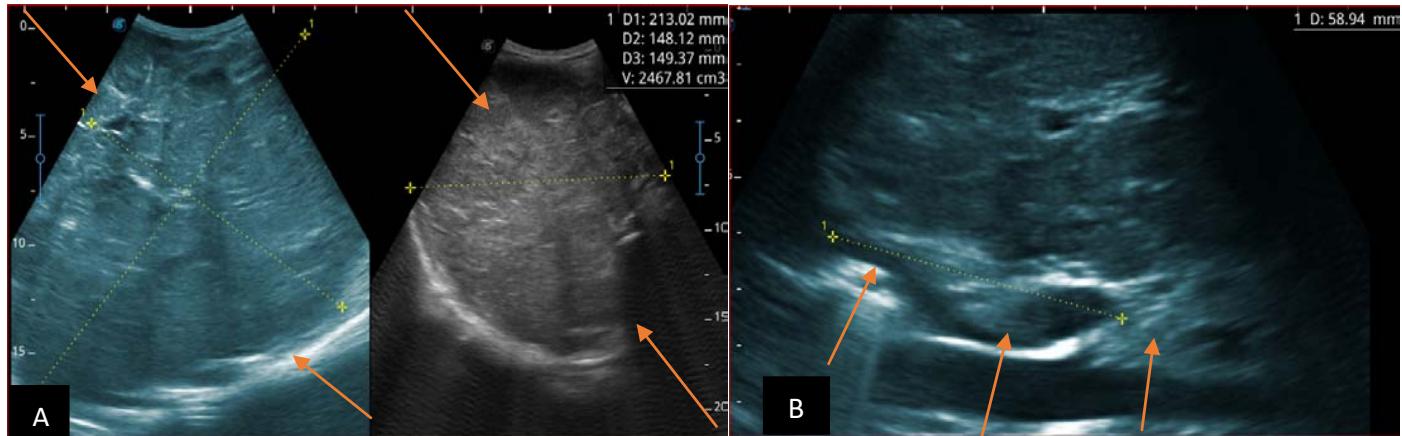

Figure 8: Patient aged 6 years, referred for abdominal bloating, in whom we noted: Image A: illustrates a right endo and exo renal solid mass, in B mode, heterogeneous, interspersed with hypo, iso and hyperechoic areas.

Images B and C: illustrate an echogenic thrombotic impregnation of the inferior vena cava. Images D-E-F: in B mode, illustrate pan-hepatic nodular lesions related to liver metastases Image G: in B mode illustrates hypoechoic coelio-mesenteric adenopathies. Images H-I: illustrates sub pleural lung parenchymal nodules in relation to lung metastases. Image J: in B mode, illustrating an echogenic pulmonary effusion, related to a hemothorax